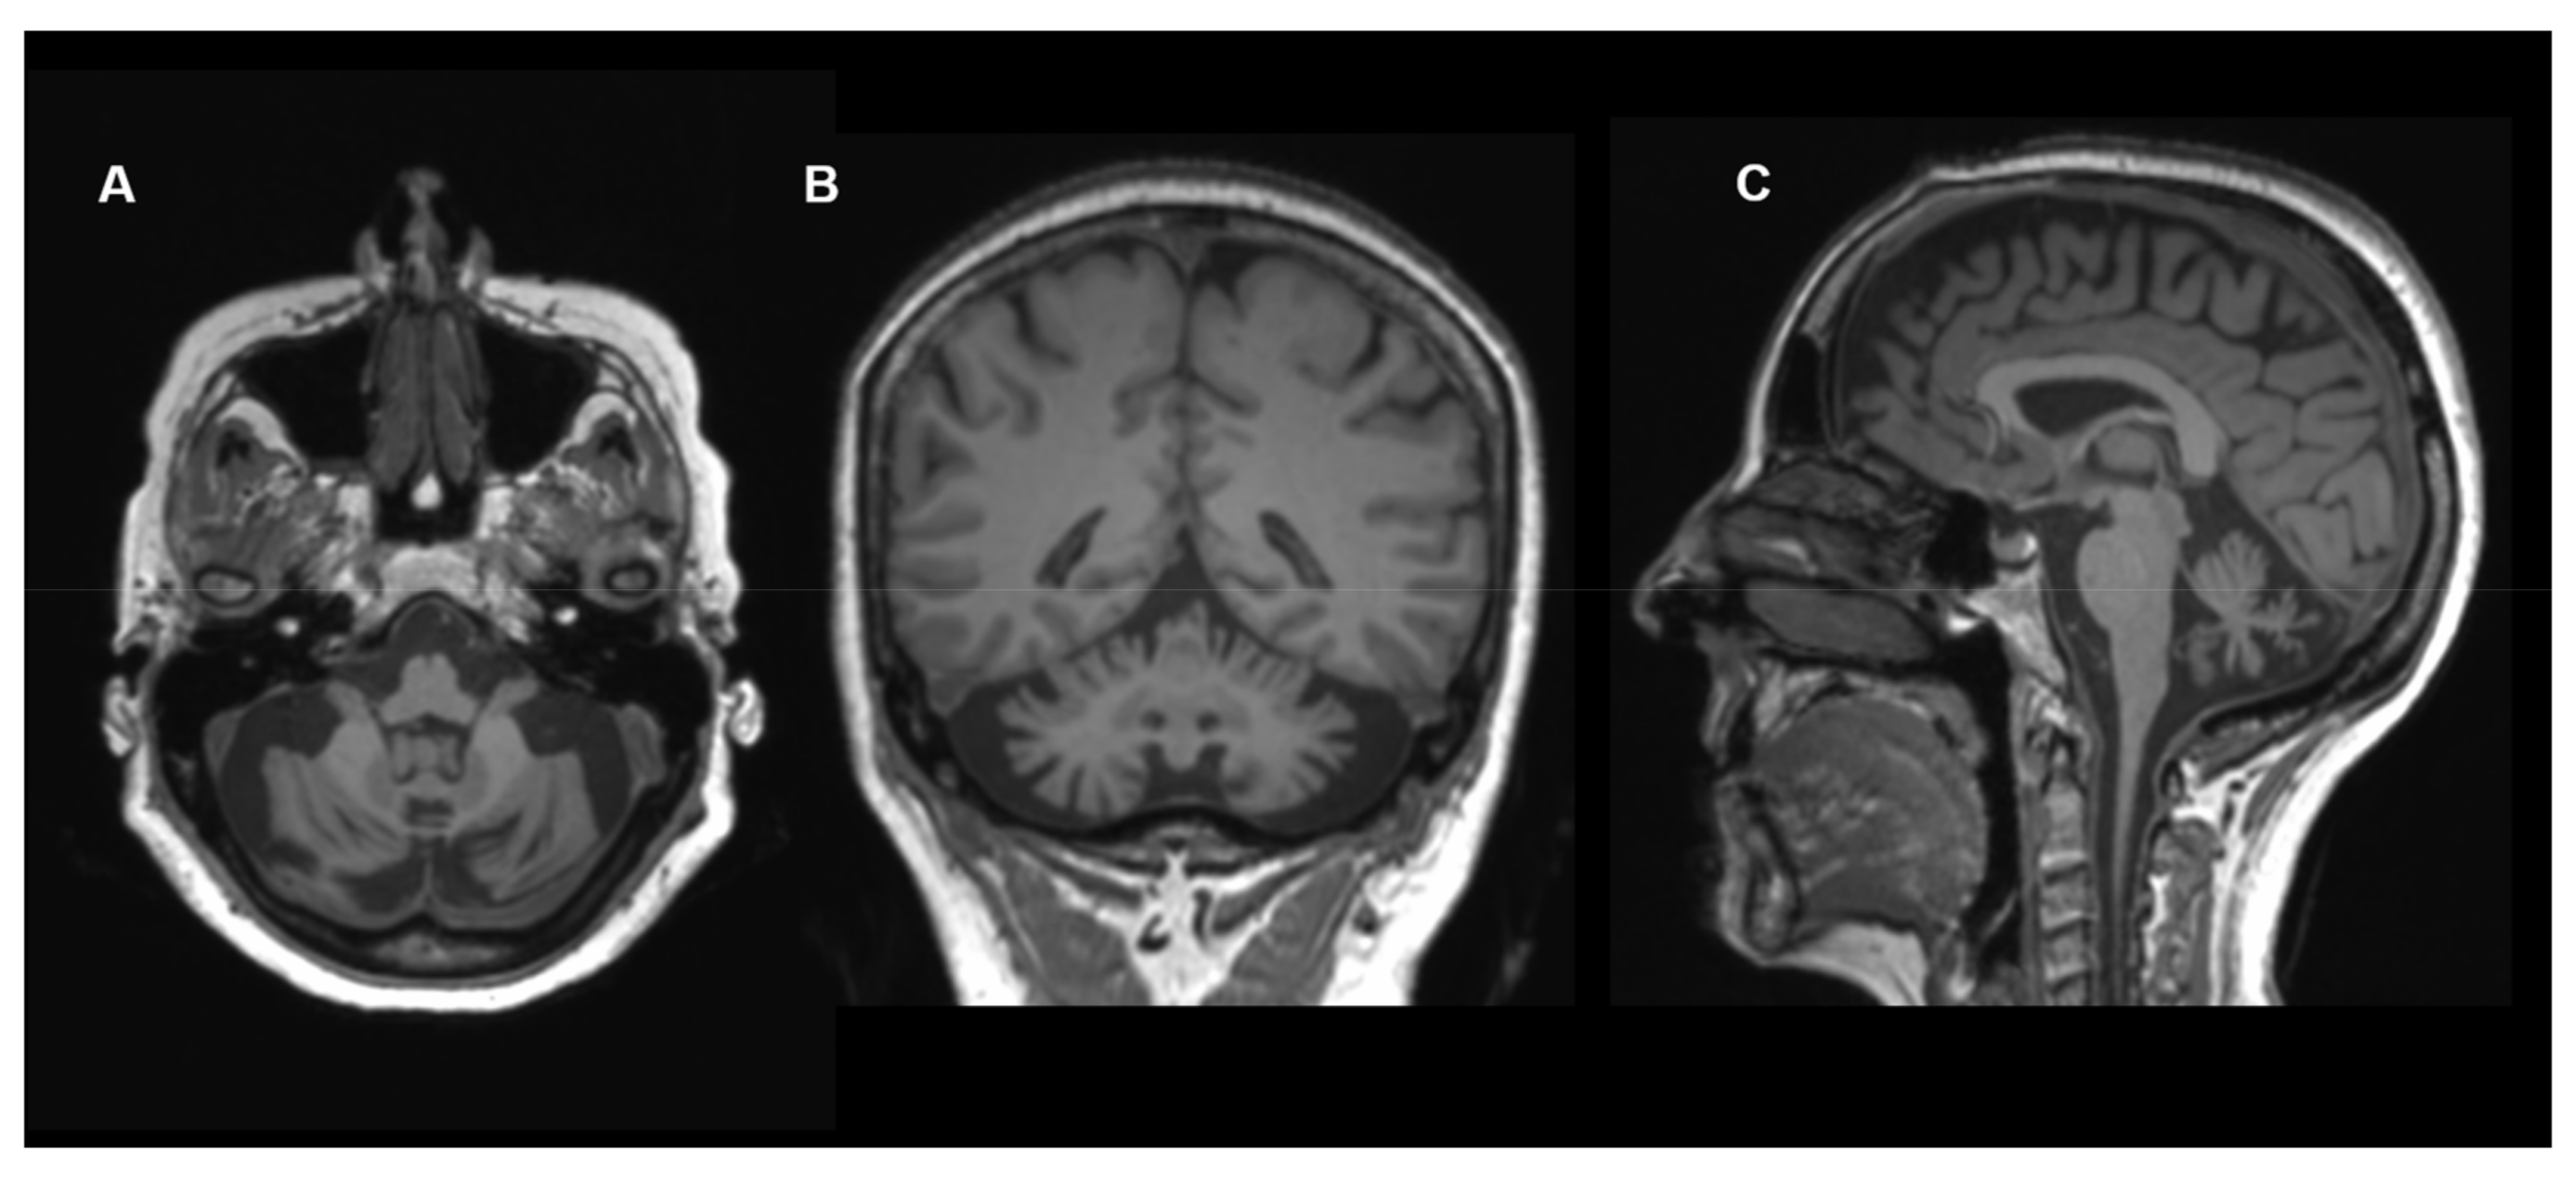

Figure 5.

Neuroimaging in COQ8A deficiency: Brain MRI (T1-weighted images, (A) axial view; (B) coronal view; (C) sagittal view) of a 60-year-old female with COQ8A deficiency. Images show cerebellar atrophy. Other MRI images of this individual were published previously [45].

COQ8A encodes for an atypical kinase-like protein relevant for CoQ10 biosynthesis [42,43,44]. Its exact function is still unclear. Disease-causing variants in COQ8A were first described in 2008 (primary coenzyme Q10 deficiency-4; COQ10D4; OMIM #612016) [44]. In 2020, Traschütz et al. published a large cohort of 59 COQ8A individuals, 54 of whom had received brain MRI [45]. They identified cerebellar atrophy as an almost universal finding (94% of patients). Less frequently, cerebral atrophy (8%), stroke-like abnormalities (8%), infratentorial signal abnormalities (4%) and brainstem atrophy (2%) were observed. No structural basal ganglia abnormalities were found. Standardized DTI in three individuals revealed changes of the infratentorial fiber tracts [45]. The findings were consistent with previous reports [44,46]. An example of cerebellar atrophy caused by COQ8A deficiency is depicted in Figure 5.

In 2020, Zhang et al. reported a 35-year-old patient who suffered neurological symptoms, such as early-onset exercise intolerance and progressive cerebellar ataxia, wide-based gait and tremors, accompanied by symptoms of dysautonomia since he was nine years old. The brain MRI showed cerebral atrophy [43].